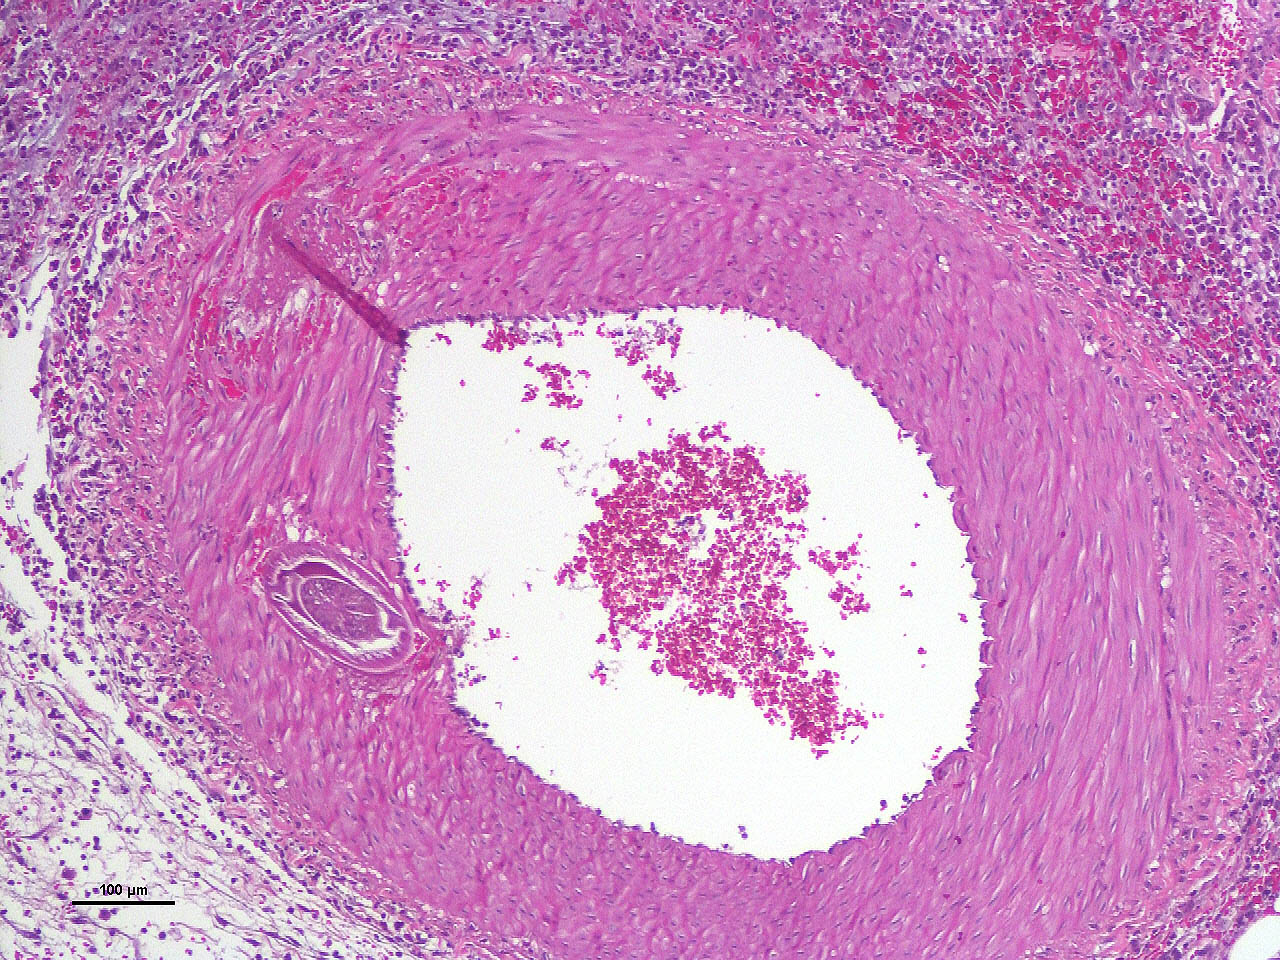

Within the media of medium to small sized arteries there were sections (not present in all slides due to the small size of the parasite – but see photomicrographs) of a nematode larva, approximately 100-200 µm in diameter with lateral allae and central digestive tract. These features are consistent with a spirurid of which Spirocerca is the most likely in our region. Foci of necrosis with hemorrhage were observed in the media of some arteries, where no larvae were identified.

Acute transmural necrotizing eosinophilic enteritis and eosinophilic peritonitis with arterial mesenteric thrombi and rare intralesional nematode larvae (spirurid)Contributor's Comment:

- Mesentery: Arteritis and periarteritis, necrotizing and eosinophilic, chronic, multifocal, severe, with arterial thrombi and rare larval spirurids.

The JPC’s own MAJ Katie Scott moderated Conference 6 and took participants on a journey of cases from around the world; each one was from somewhere outside of the continental U.S., highlighting the truly global nature of the WSC and the importance of international contributions to pathology education. This first case provided an excellent opportunity to review of the pathogenesis and life cycle of Spirocerca lupi, both of which are well-covered in the contributor’s comment. Additionally, the lesions of spirocercosis that are considered pathognomonic in the dog were covered and include aortic scarring with aneurysms, thoracic spondylitis, and caudal esophageal nodules. Special attention was paid to the chronic arterial thrombi present in numerous arteries in this case, which are a classic part of the pathogenesis of this parasite due to its arterial migratory routes and chronic intimal irritation. Participants were also reminded of the importance of specifying what type of vessels (arteries, arterioles, veins, lymphatics, etc.) are affected when giving a description, as this can provide important clues towards pathogenesis of some diseases that may preferentially affect a specific vessel type.Spirocerca lupi is one of a handful of helminths that are classified as Group I carcinogens by the International Agency for Research on Cancer (IARC) due to the well-documented malignant transformation of S. lupi esophageal nodules into esophageal fibrosarcomas or osteosarcomas in up to 25% of infected dogs.6 Less commonly, chondrosarcomas or undifferentiated pleomorphic sarcomas can also be seen.6 Metastasis to multiple locations throughout the body, including the lungs, kidneys, stomach, spleen, heart, and tongue, occurs frequently.6,7 Significantly higher levels of interleukin-8 (IL-8) have been documented in dogs with malignant esophageal nodules.4 IL-8 is released by activated fibroblasts in pre-neoplastic nodules and is chemotactic for neutrophils. IL-8 is also involved in the tumor progression of human herpesvirus-4 (Epstein–Barr virus)-induced carcinomas.4